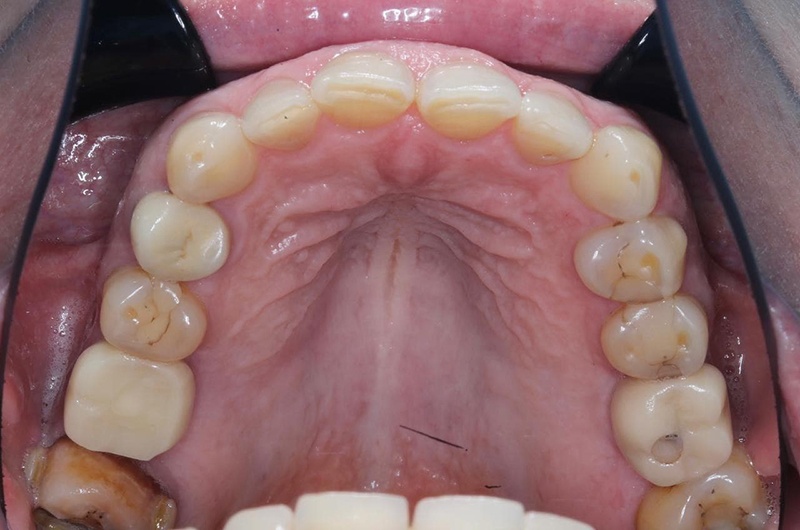

Верхняя челюсть

Что у нас было на входе? С правой стороны когда-то были удалены шестой и седьмой зубы, восьмой съехал на место седьмого. С левой — удалён шестой, седьмой с не очень удачно пролеченными каналами, в восьмом огромная полость. Шестой был удалён так давно, что седьмой практически полностью теперь на его месте. Восьмой лежит, не прорезавшийся. Тёмное пятно вокруг седьмого ничего хорошего не говорит, за корнем какая-то проблема локализуется.

Что имеем на этом этапе? У пациентки удалена верхняя восьмёрка, установлен ортоимплант, который будет тянуть семёрку на своё родное место. Установлена резиновая тяга. Удалена нижняя семёрка и нижняя восьмёрка, установлены импланты на правой стороне.

Сейчас у пациентки установлены временные коронки на всех имплантах, она уже может ими жевать. Мы планово ждём, когда сможем заменить все временные коронки на постоянные и робко надеемся, что за это время не случится падения метеорита на землю или зомби-апокалипсиса.

Установленные временные коронки. Объект на шестом зубе легко принять за кариес, но на самом деле это шахта винта, который держит временную коронку на импланте. В общем, зуб выглядит сейчас страшненько, но это живое фото в процессе лечения. Новых фото, где он уже совсем здоровый и красивый, пока ещё нет. Кстати, если бы кариес на этом зубе был, то есть когда у нас не тотальная реставрация зубов, а какие-то небольшие полости, мы бы лечение не задваивали, а устраняли бы дефекты уже во время финальной реставрации. При тотальной реставрации мы бы всё зачистили заранее.